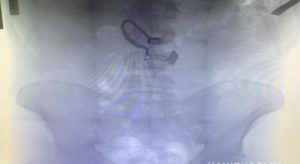

- рентген;

- пальпация брюшной полости;

- радиографическое исследование;

- эндоскопия;

Стоит отметить, что именно рентген является лучшим способом диагностики. Благодаря данной процедуре, можно увидеть камни, различные предметы и другие инородные тела, которые оказались в организме собаки.

- Рентген. Во время исследования бывают хорошо видны камни, металлические и резиновые предметы. Или же, если инородное тело не определяется, врач может заметить изменения внутренних органов, характерные для наличия инородного тела.

- Радиографическое исследование. Для отслеживания продвижения предмета по желудку и кишечнику используется контрастное вещество (чаще всего барий), которое задается собаке внутрь.

- Эндоскопия. На сегодня считается самым лучшим методом диагностики инородного тела.